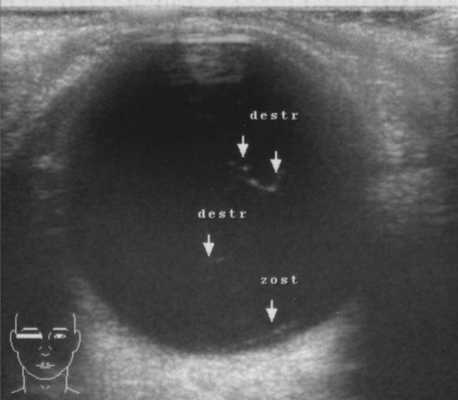

При переднем увеите (55 пациентов, 106 глаз) по всей поверхности эндотелия роговицы наблюдали множественные крупные сальные преципитаты, иногда гранулематозные узелки в строме и по зрачковому краю радужки, задние синехии; также выявляли клеточную инфильтрацию и деструктивные изменения в стекловидном теле (рис. 3). Рисунок 3. В-сканограмма правого глаза (OD) больного Н., 47 лет. Деструктивные изменения стекловидного тела c клеточной инфильтрацией. Отслойка задней гиалоидной мембраны.